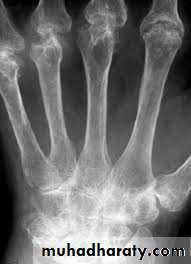

RHEUMATOID ARTHRITISFema1e:male = 3:lRadiographic features

Early changes

* Peri articular soft tissue swelling (edema, synovial congestion)

*Peri articular osteoporosis in symmetrical distribution (hallmark)

* Preferred sites of early involvement

Hands: 2nd and 3rd MCP joint

Feet: 4th and 5th MTP joint

Late changes

*Erosions (pannus formation, granulation tissue) first attack joint portions in which protective cartilage is absent (i.e., capsular insertion site).

* Erosions of the ulnar styloid and triquetrum are characteristic.

* Subchondral cysts formation results from synovial fluid, which is pressed into bone marrow through destroyed cartilage.

Subluxations , Carpal instability and ulnar deviation .

* Fibrous ankylosis is a late finding.

Gross rheumatoid arthritis at the carpus with ulnar deviation,

subluxation and joint narrowing at the metacarpophalangeal joints.Boutonniere deformities are present at the index and little fingers.